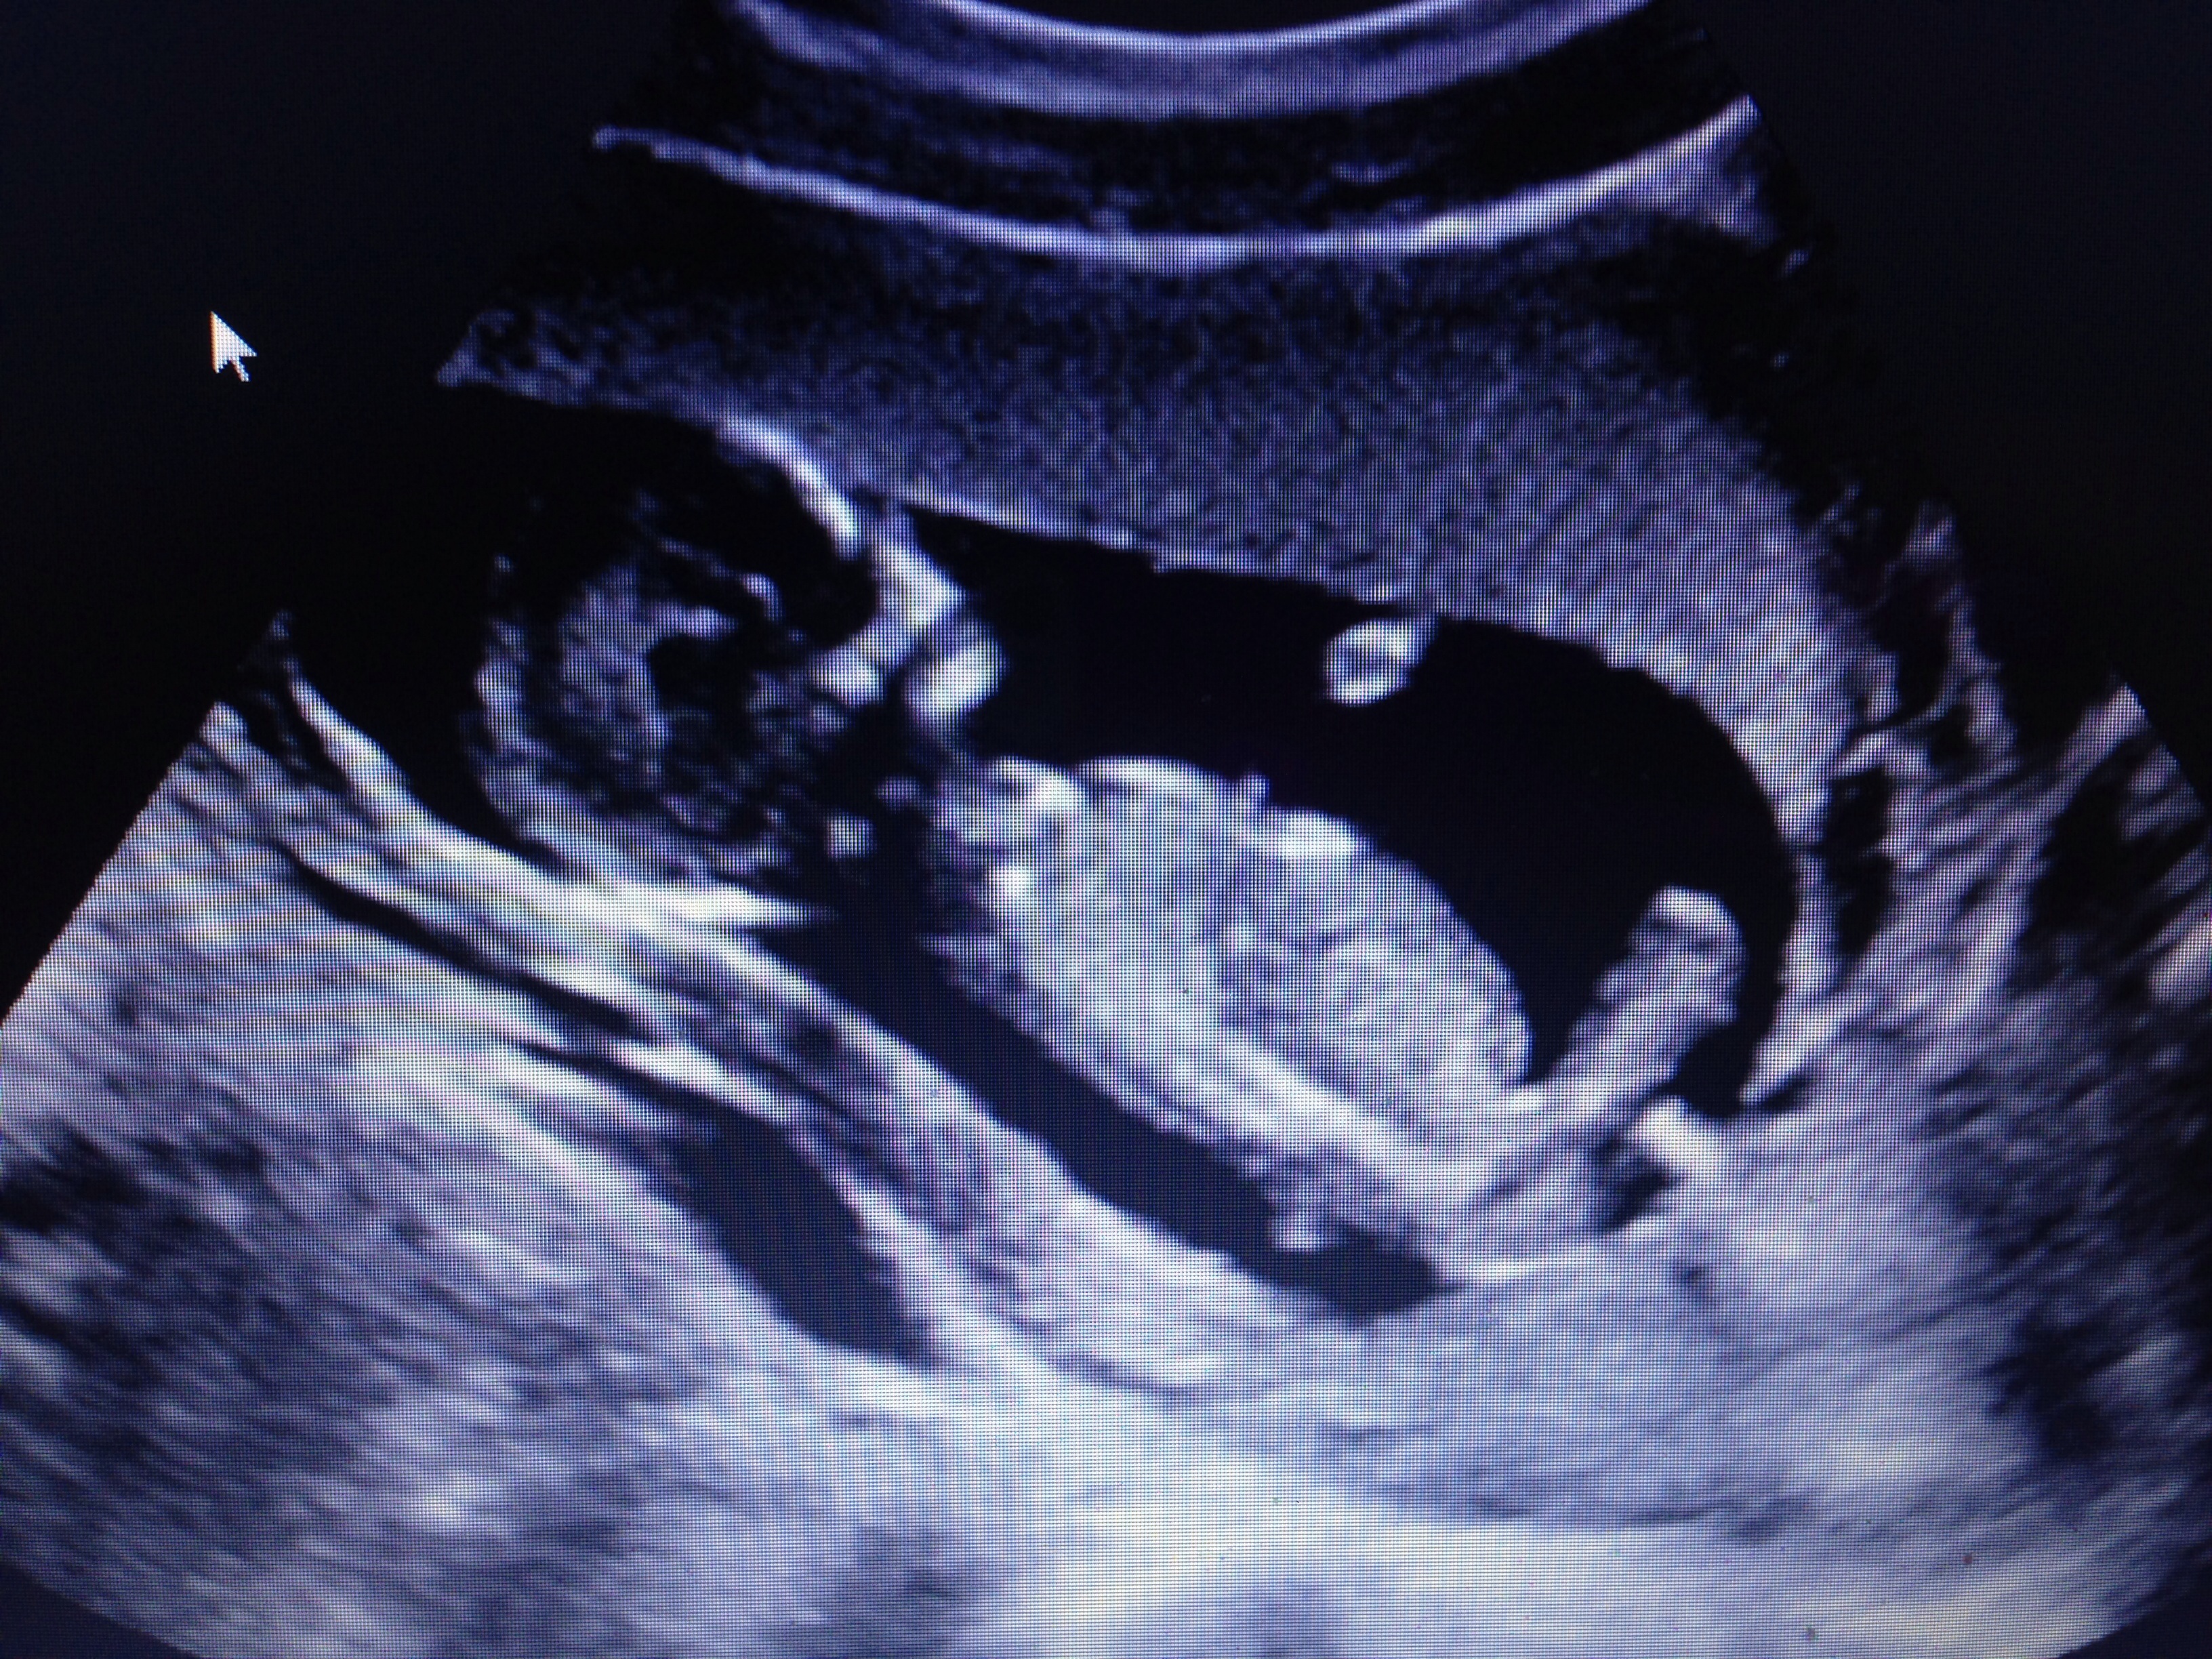

I've been lurking since I was 4 weeks along. I waited to do an intro because I was worried it wouldn't work out, but after having my N/T scan this morning I'm finally starting to get excited and wanted to share! I'm 20 years old and this is my first pregnancy. Baby is measuring at 14+1 instead of 13+4 and looks healthy and happy. I got to see baby sucking his/her thumb and being able to see that has made me feel much better and excited about this whole thing!